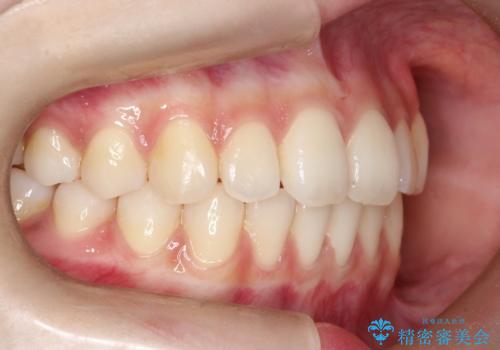

【前歯で噛めません、すきっ歯も気になります】インビザライン治療症例

- 前歯の見た目と噛み合わせの改善を希望され来院された患者様です。

初診時の歯並びの状態としては、上下前歯が噛んでいない開口という状態であり、前歯を中心に上下とも歯の間に隙間がある状態でした。

抜歯は行わずマウスピース治療による主訴の改善を計画しました。

また、開口、スキッ歯の根本的な原因として考えられる、舌突出癖による後戻りの防止のためにMFTという舌のトレーニングも行いました。

見た目、嚙み合わせ及び、治療期間や施術内容に大変ご満足いただきました。